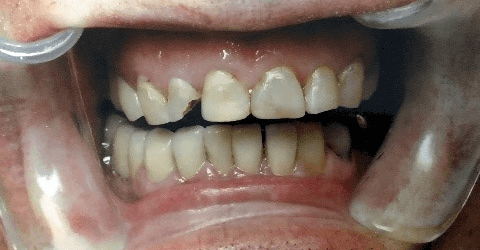

Not happy with your smile? Dr. Tom and Dr. Seth are happy to help! With years of experience and the latest in dental materials technology Daniels Family Dentistry will have you smiling in no time. Whether it’s a chipped or broken tooth, a cavity, or dark, stained teeth we can help. Offering a full range of bleaching services, veneers, as well as fillings, crowns and implants we can use these tools to help correct and improve your smile. If your teeth need to be straightened or moved, we have good relationships with orthodontists in the area to get a great result by working together with them on an overall plan. By coordinating with these highly skilled orthodontists and oral surgeons we can make sure you get the smile you deserve.

Through the use of crowns (caps) we are able to take broken down and stained teeth and restore them to be more pleasing.